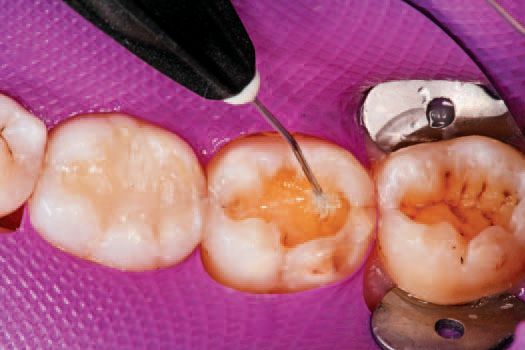

A single increment of Tetric EvoCeram Bulk Fill in shade IVA was then placed in the preparation of tooth No. 30 (Fig. 9), and shaped first with an OptraSculpt® sphere attachment (Fig. 10), then with an OptraSculpt pyramid attachment (Fig. 11). The final anatomy was contoured using a P1 plugger (Fig. 12). As a final step before finishing, the restoration was light cured with the LED curing light (Fig. 13).